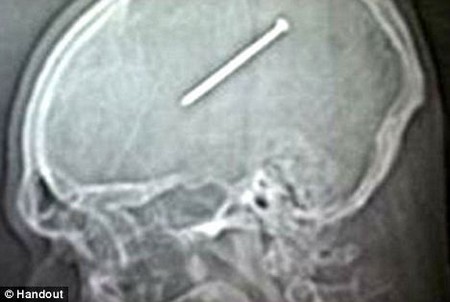

Một người đàn ông tại Mỹ đã vô tình bắn vào đầu mình một chiếc đinh dài đến 9 cm bằng súng bắn đinh, tuy nhiên vẫn giữ cho chiếc đinh nằm trong đầu gần 2 ngày, trước khi quyết định đến bệnh viện để nhờ sự trợ giúp của bác sĩ.

Dante Autullo, 32 tuổi, đã vô tình bắn chiếc đinh vào đầu mình bằng súng bắn đinh khi đang sửa lại căn nhà của mình ở Chicago (Mỹ). Autullo tin rằng mình đã vô tình nhấn vào nút bắn đinh khi đang đưa chiếc súng bắn ngang qua đầu mình.

Chiếc đinh dài 9cm nằm trong đầu Autullo gần 2 ngày mà anh không hay biết

Hôn thê của anh, Gail Glaenzer, lập tức đưa Autullo đến bệnh viện gần nhất để kiểm tra. Tại đây, các bác sĩ đã hết sức bất ngờ khi kết quả chụp phim X-Quang cho thấy một chiếc đinh dài đang nằm giữa đầu của Autullo.

Rất may, vị trí của chiếc đinh chỉ cách phần chức năng kiểm soát vận động của não bộ vài mm, do vậy Autullo vẫn có thể hoạt động bình thường sau khi chiếc đinh đi vào đầu.

Autullo đã lập tức được tiến hành phẫu thuật và các bác sĩ đã lấy chiếc đinh ra thành công sau ca đại phẫu kéo dài 4 tiếng. Các bác sĩ đã phải thay thế phần hộp sọ bị chấn thương của Autullo bằng hợp chất titan.